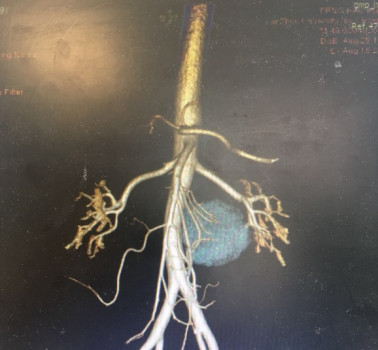

术前对患者进行了精确的术前评估,为明确肿瘤与周围组织关系,并进一步制定手术方案,在与患者及其家属的同意下,利用3D打印技术,明确了肿物与周围组织的关系及其血供。经过全科医师的讨论,肿瘤解剖位置靠近腹主动脉,腹腔镜在后腹膜位置操作困难,难以及时对大血管的损伤进行止血,为避免术中大出血,而造成难以挽救的结局,决定以剖腹方式进行手术。

图2 蓝色为肿瘤